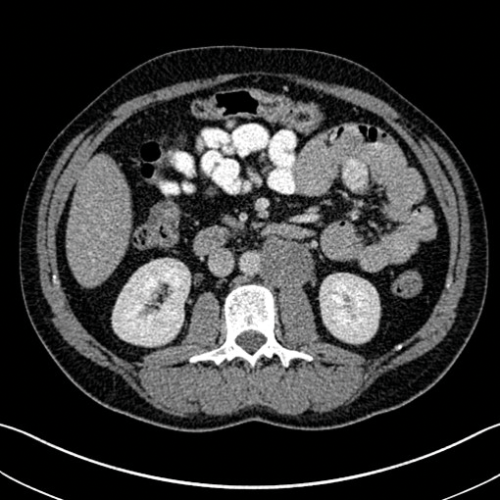

Figure 4. Axial CT showing aortocaval lymph node from a right sided tumour.

Stage two disease has abdominal lymph nodes; 2a nodes <2cm, 2b nodes 2-5cm, 2c at least one node >5cm. Retroperitoneal lymph nodes are the commonest site for metastatic disease and left sided tumours tend to spread to left para-aortic lymph nodes (Figure 3) and right sided tumours to aorto-caval or precaval nodes [3] (Figure 4). It is important to carefully evaluate the relevant area depending on the site of the tumour.